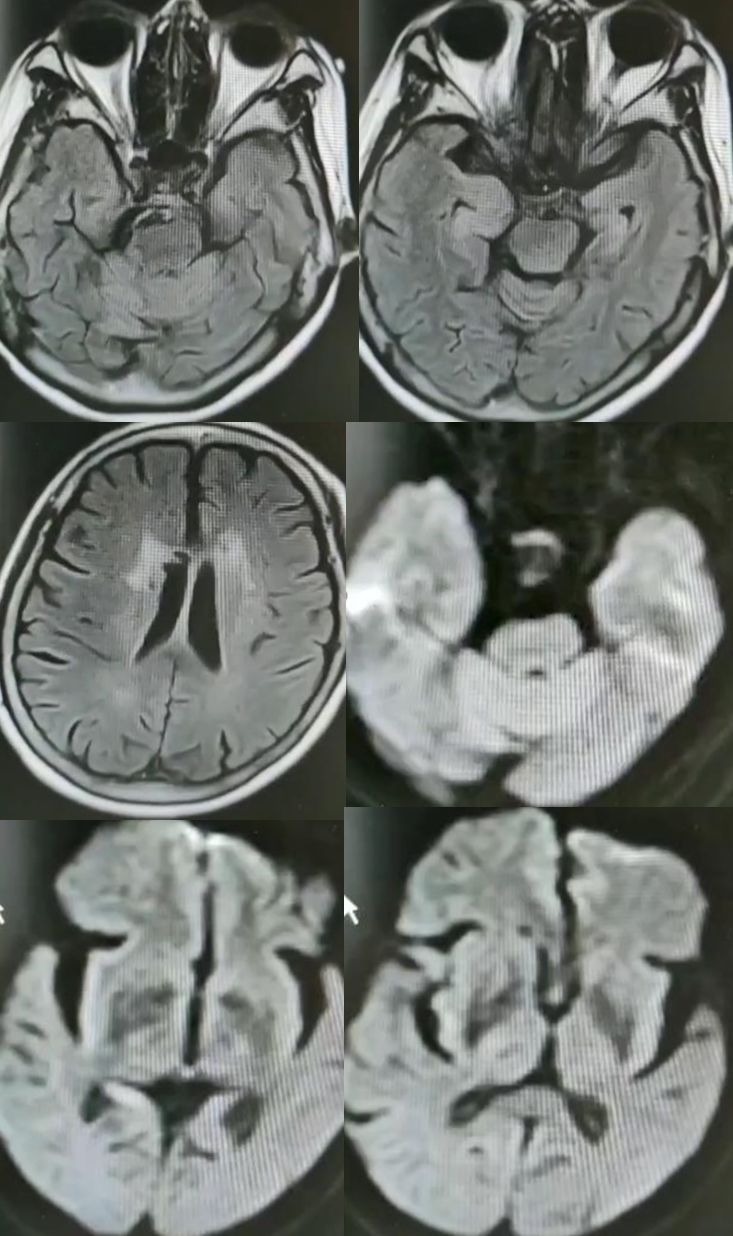

病例12

女性,75岁,发作性抽搐半月,意识障碍2天。

答案:抗GABABR抗体相关脑炎。抗GABABR抗体相关脑炎在临床上符合边缘性脑炎的表现,通常以癫痫发作、记忆力减退和意识障碍为主要特征。表现形式多样的癫痫发作是早期最突出的特征,多为继发性全身发作,还可以表现为复杂部分性发作、全面发作、全面强直-阵挛性发作、部分性运动性发作,甚至出现癫痫持续状态。患者多合并有记忆力减退和意识障碍,病程后期甚至出现幻觉和人格改变。癫痫发作也可以作为其唯一的表现。约有50%的GABABR抗体阳性患者合并小细胞肺癌,少数可合并其他肺部神经内分泌肿瘤、黑色素瘤及良性胸腺瘤等肿瘤。头MRI一侧或两侧内侧颞叶FLAIR/T2像信号增高提示该诊断的可能,但是这也见于其他自身免疫性脑炎。